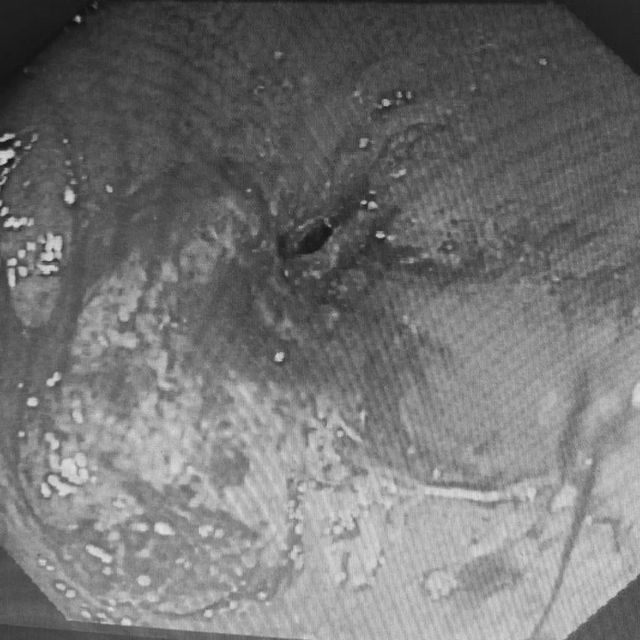

如罗晓华护士长之前判断一样

老人为食管恶性肿瘤占位,食道肿物基本已经环周,只留下了一个非常细小的管腔,正常胃镜根本无法通过,并且肿物稍微触碰摩擦就出现渗血出血的情况,并且老人身体衰弱,难度和风险很大。

王业忠副主任医师改变策略

选择更换鼻内镜下镜

尽可能减少对老人食管的损伤

最终在导丝引导下成功置入